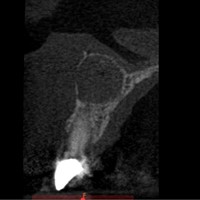

Pacjent z bólem, nieudana próba udrożnienia kanałów pod mikroskopem. Decyzja o resekcji korzenia policzkowego dalszego. RTG kontrolne rok po zabiegu.